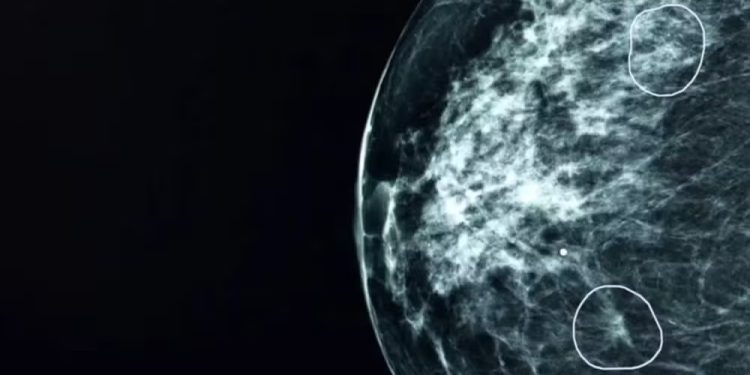

Uma ferramenta de Inteligência Artificial, conhecida como Mia, revelou sintomas até então não detectados de câncer de mama em exames de 11 mulheres durante um teste conduzido no Reino Unido. Esta ferramenta, desenvolvida em colaboração com o NHS, identificou com precisão pequenos indícios de câncer de mama que haviam escapado da detecção pelos médicos. Mia foi submetida a testes em conjunto com profissionais de saúde do NHS, analisando mamografias de mais de 10 mil mulheres.

Apesar da maioria dos exames não revelar sinais de câncer, Mia conseguiu detectar corretamente todos os casos em que médicos haviam apontado indícios, além de identificar 11 casos adicionais em que os tumores não haviam sido detectados anteriormente. A detecção precoce do câncer é crucial, já que os tumores em estágios iniciais podem ser extremamente pequenos e difíceis de identificar.

Um exemplo real da eficácia de Mia foi observado quando a ferramenta identificou tumores praticamente invisíveis aos olhos humanos durante uma demonstração realizada pela BBC em um hospital do NHS. Uma paciente, Bárbara, teve seu câncer detectado precocemente pela ferramenta, o que possibilitou um tratamento menos invasivo, resultando em apenas cinco dias de radioterapia.